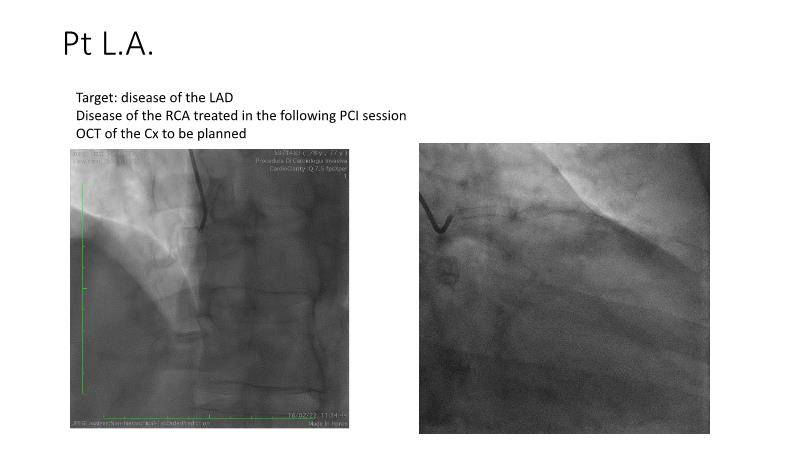

Join this session to explore the revolutionary Dynamx Bioadaptor and its role in restoring vessel physiology and function. Learn about the specific patient and lesion characteristics that can be safely and effectively treated with this innovative device, gain confidence in the delivery and deployment techniques, understand its unique design characteristics and explore the evidence supporting the benefits of vessel restoration.

- To know the patients and lesions that can be safely and effectively treated with Dynamx Bioadaptor

- To be able to approach the delivery and deployment of the Dynamx Bioadaptor with confidence

- To understand the unique design characteristics of Bioadaptor and evidence supporting vessel restoration benefit